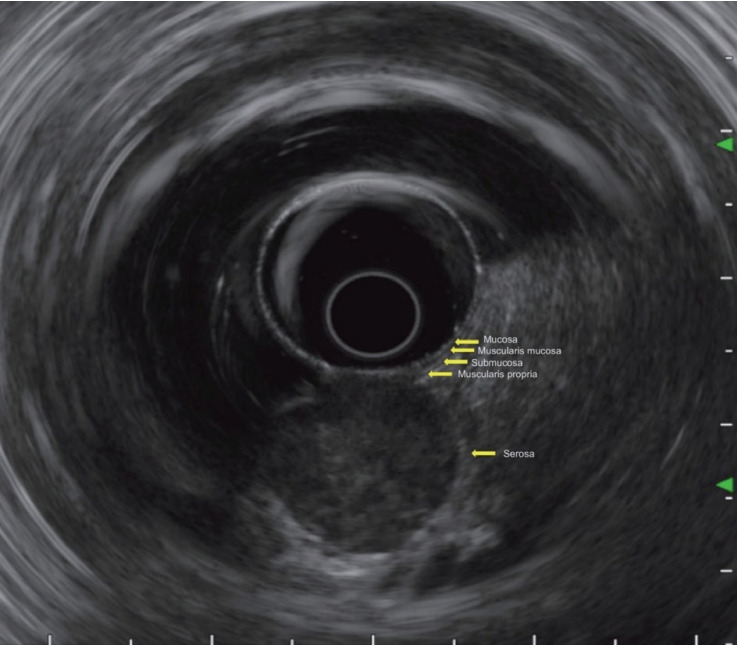

胃上皮下病变(SELs)的检测随着内镜筛查的广泛使用而增加。虽然大多数SELs是良性的,但有些,如胃肠道间质瘤,有恶性的可能,这强调了准确诊断的重要性。由于这些病变位于粘膜下,组织学确认往往具有挑战性,这限制了传统活检技术的有效性。超声内镜(EUS)在病变表征中起着核心作用,它提供了关于起源层、回声性和内部特征的信息。当需要组织取样时,粘膜切口辅助活检(MIAB)和eus引导的细针活检(FNB)等技术具有互补的优势。MIAB的诊断率约为89%,特别是对病变

The detection of gastric subepithelial lesions (SELs) has increased with the widespread use of endoscopic screening. While most SELs are benign, some, such as gastrointestinal stromal tumors, have malignant potential, underscoring the importance of accurate diagnosis. Histological confirmation is often challenging due to the submucosal location of these lesions, which limits the effectiveness of conventional biopsy techniques. Endoscopic ultrasonography (EUS) plays a central role in lesion characterization, providing information on the layer of origin, echogenicity, and internal features. When tissue sampling is required, techniques such as mucosal incision-assisted biopsy (MIAB) and EUS-guided fine-needle biopsy (FNB) offer complementary advantages. MIAB has demonstrated a diagnostic yield of approximately 89%, particularly for lesions <20 mm, whereas FNB provides sufficient tissue for immunohistochemical analysis. As international guidelines differ regarding indications and methods of tissue acquisition for SELs, tailored management based on EUS findings, patient-specific factors, and institutional capacity is essential for optimal diagnostic outcomes. This review aims to summarize the current understanding of gastric SELs based on evidence-based guidelines and recent studies and offer practical guidance for clinicians diagnosing these lesions in routine practice.